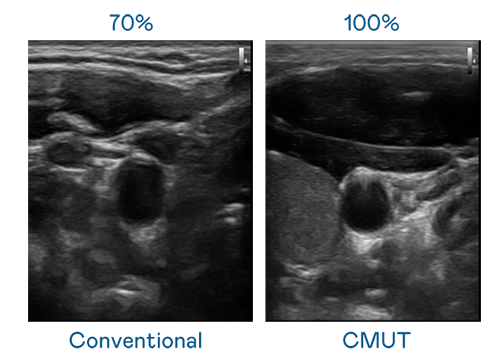

CMUT 技术是一种用电容式微机电元件来产生超音波讯号的技术。与传统 PZT 压电式技术相比,CMUT 频宽增加 30%,更宽频的超音波讯号让影像解析度大幅提升,是实现高影像品质医疗超音波扫描、促进精准医疗发展的关键技术。

大频宽带来超清晰影像

超音波影像的解析度高低,首先取决于探头能发出的讯号频宽。尊龙 CMUT 可提供高清晰的超音波讯号,提供高频宽、高灵敏度、影像纹理细节更高的超音波影像,协助医护人员缩短影像判读时间及利用精准的医疗影像进行诊断。